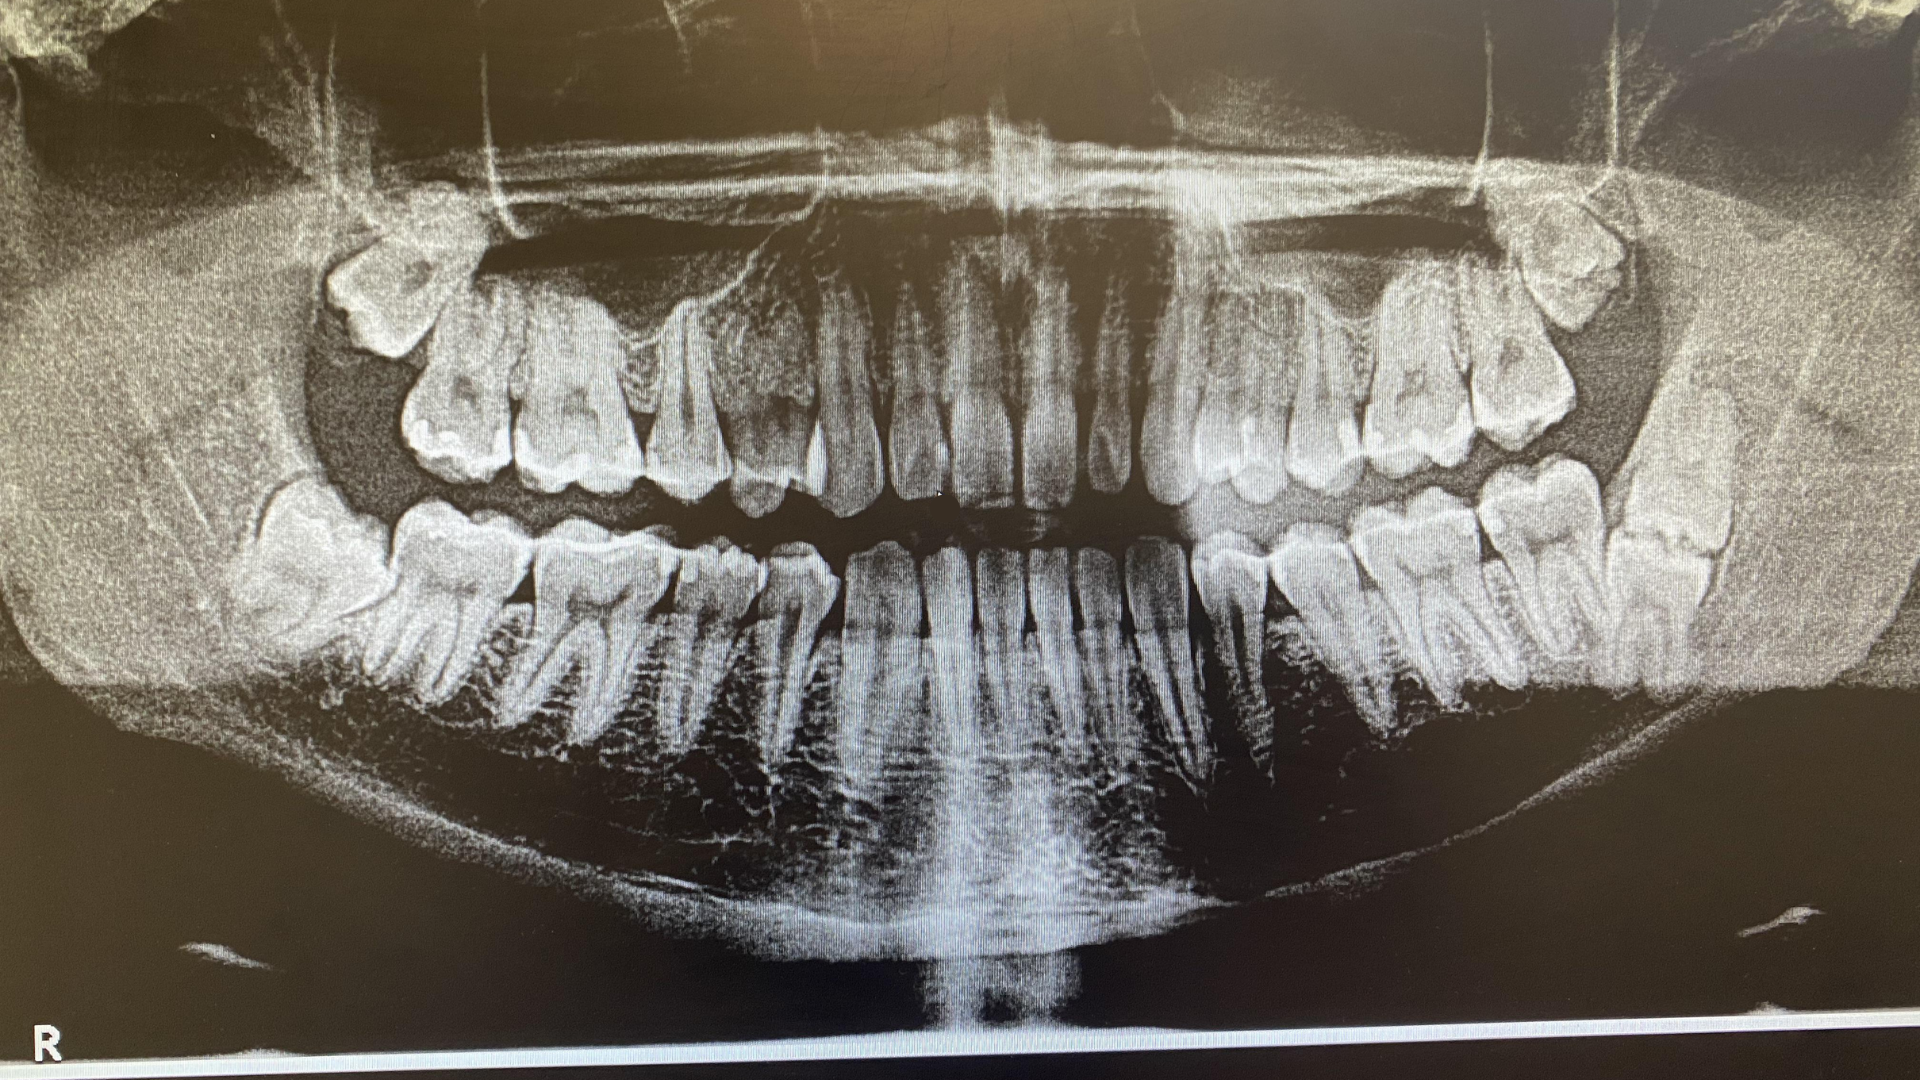

Vì vậy, chẩn đoán hình ảnh qua phim X-quang là bước bắt buộc để phân biệt chính xác các tình trạng này.

Khi đến khám với nghi ngờ có hay không tình trạng mọc 5 răng khôn, người bệnh sẽ được bác sĩ thăm khám lâm sàng trực tiếp để đánh giá tình trạng nướu và cung hàm. Bước tiếp theo là chụp X-quang toàn hàm hoặc phim cắt lớp nếu cần để xác định chính xác số lượng, vị trí và hướng mọc của tất cả các răng trong xương hàm. Dựa trên kết quả, bác sĩ sẽ tư vấn kế hoạch theo dõi hoặc can thiệp phù hợp với từng trường hợp cụ thể.